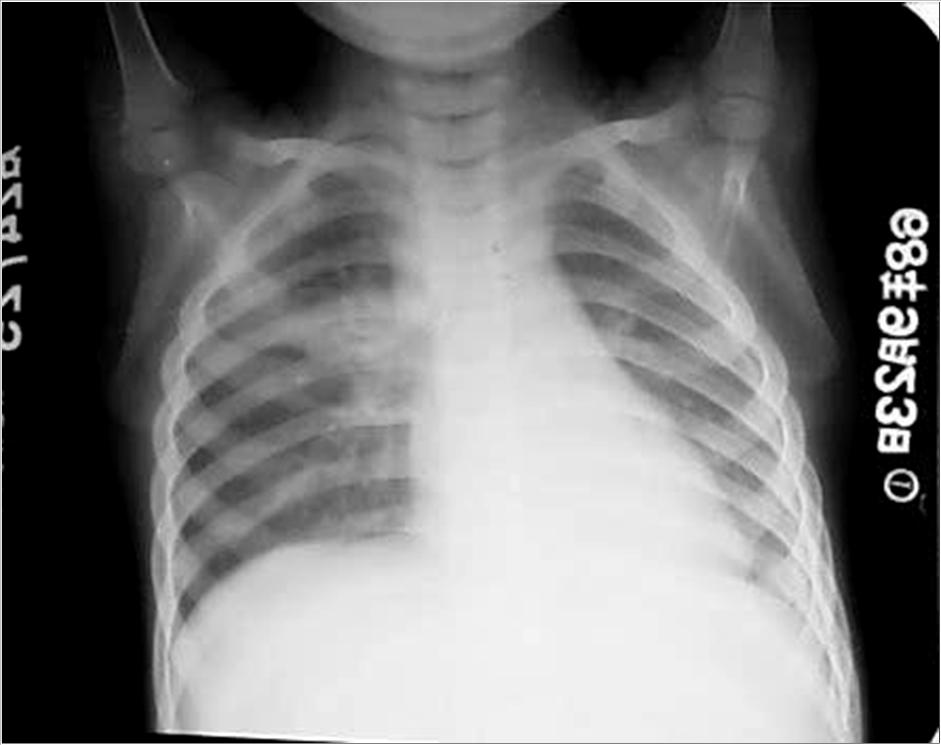

看看这小孩的肺原发综合征

原发综合征 右下肺原发病灶, 淋巴管炎,淋巴 结炎三者组成典 型征象